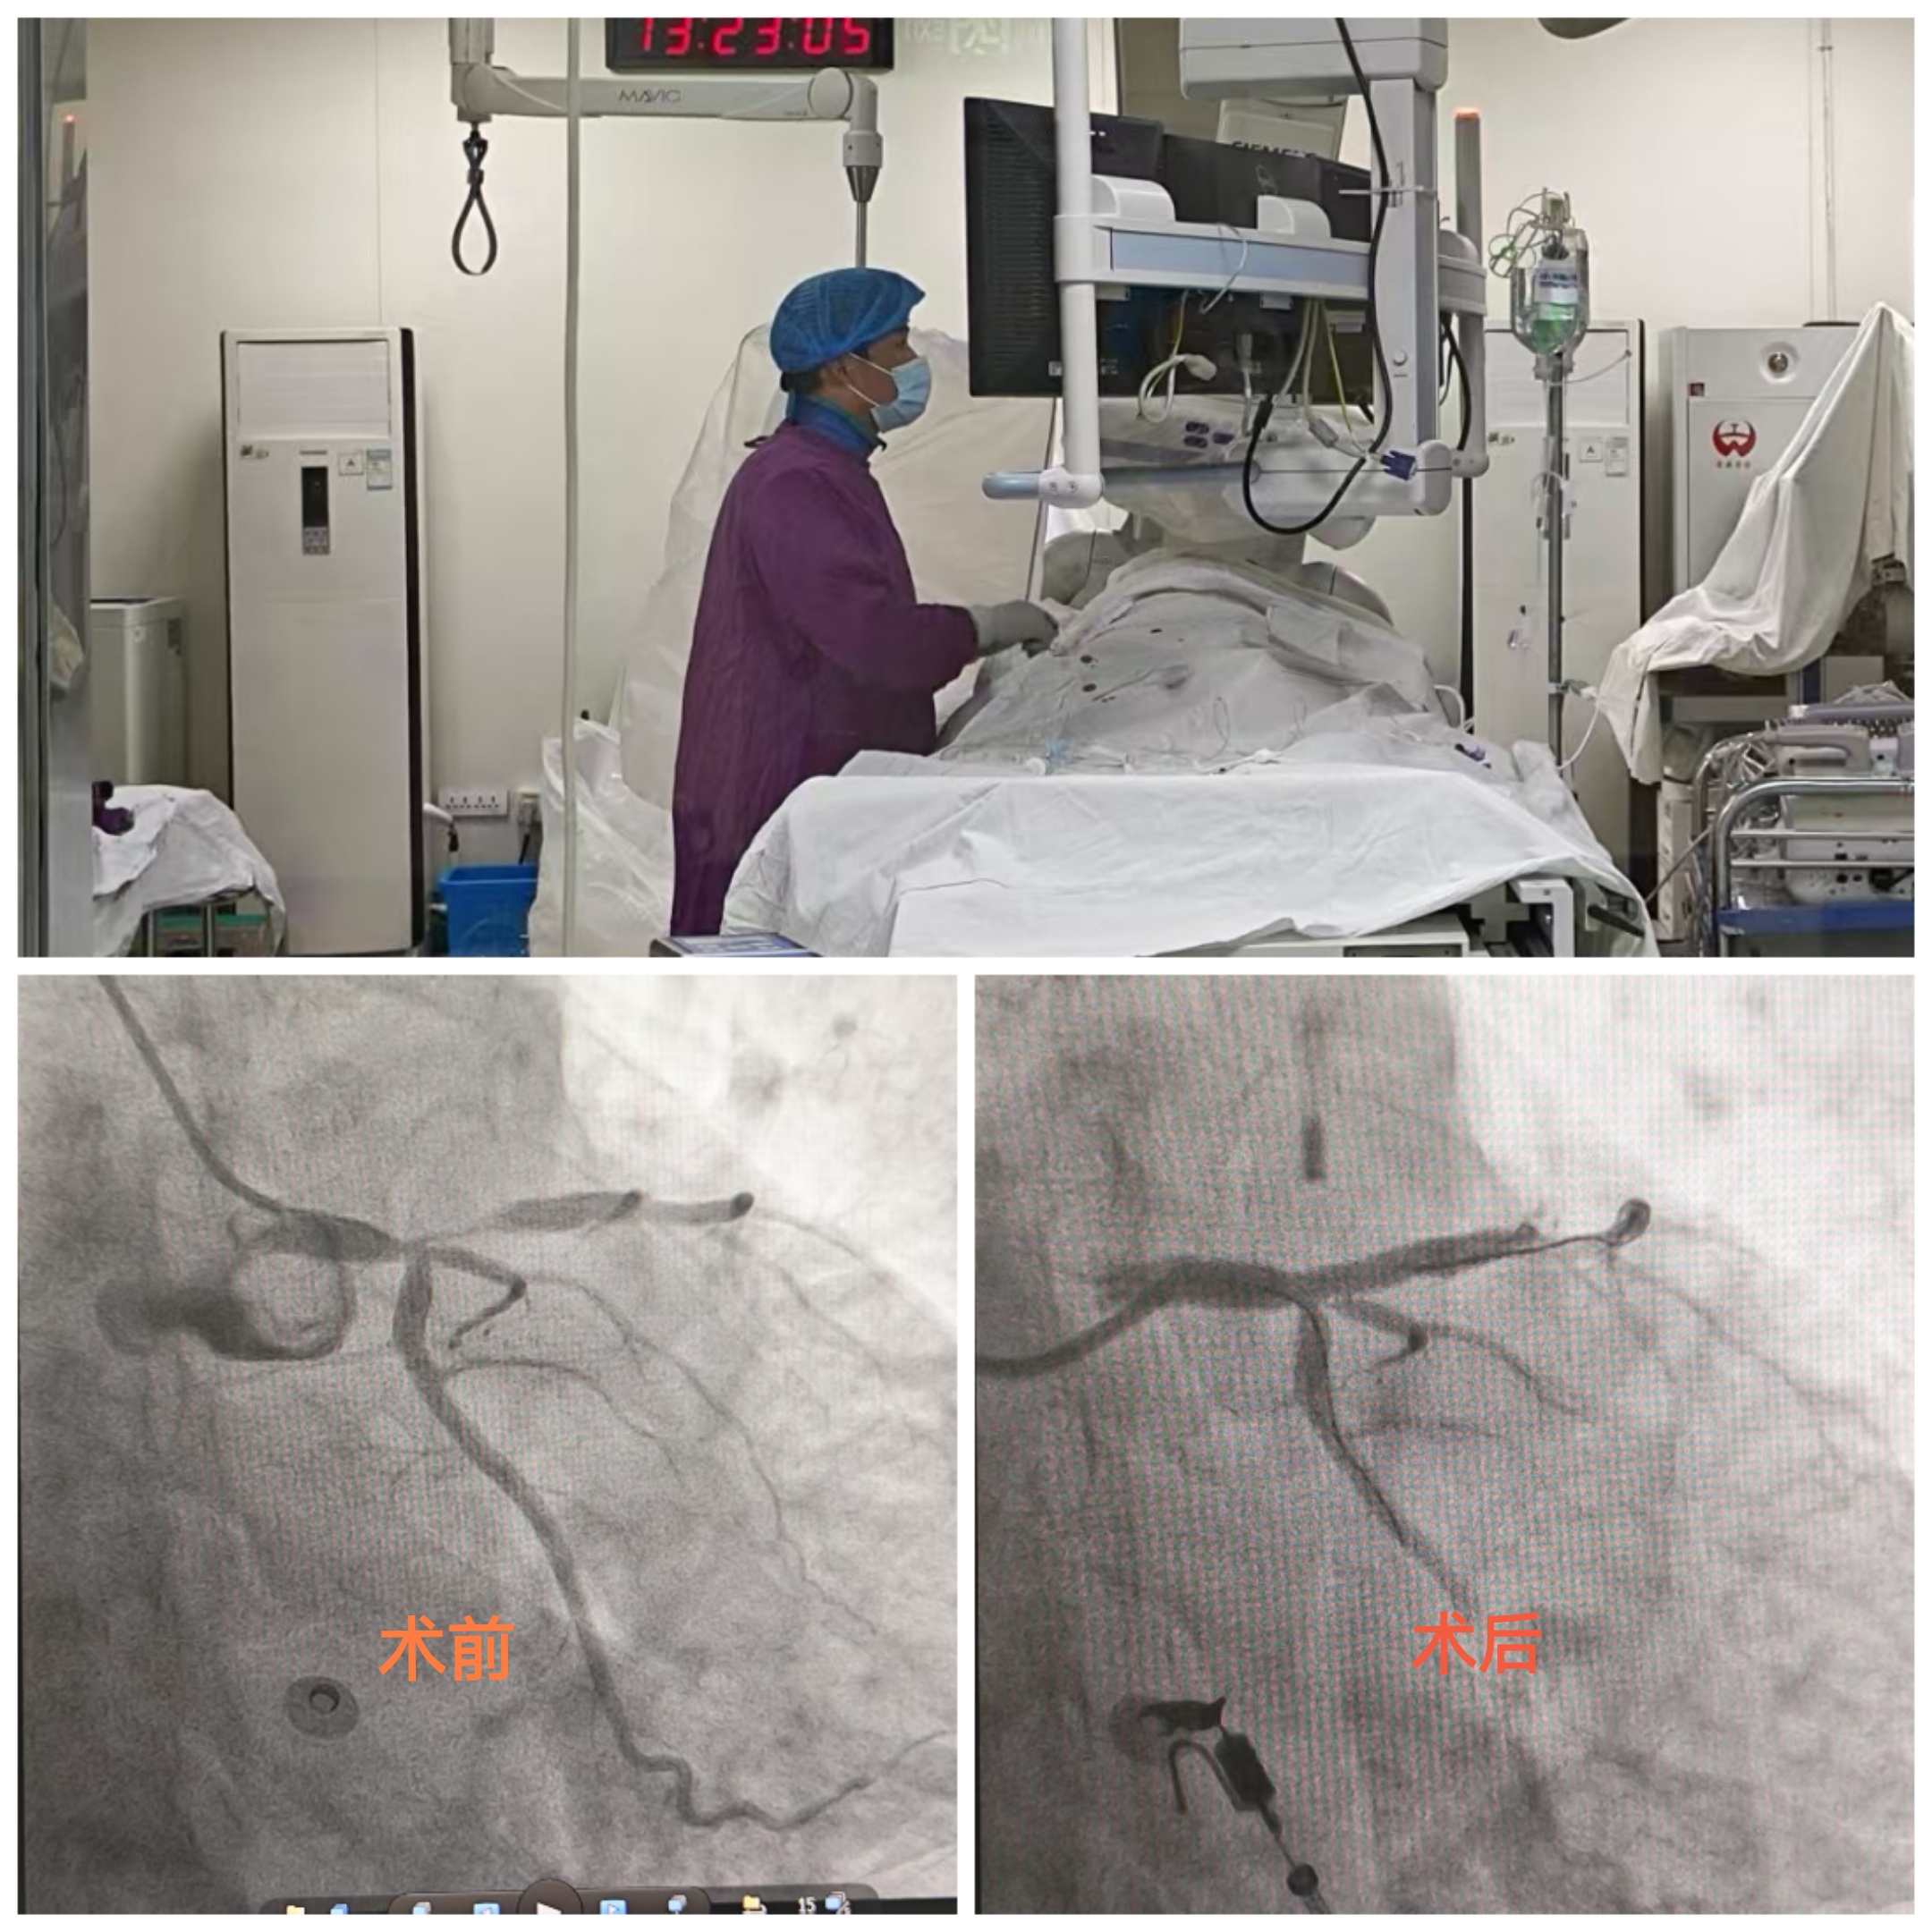

一位老人在健康管理中心进行健康体检,行心电图检查时提示V1-V5异常Q波伴ST段抬高,T波改变。经验丰富的心功能科医生敏锐捕捉到异常波形,凭借专业的医学判断,高度怀疑患者为急性心肌梗死。心功能科医生立即按危急值流程通知健康管理中心医护人员。健康管理中心迅速开通绿色通道,安排患者立即前往胸痛门诊就诊。胸痛门诊医护团队第一时间启动胸痛中心患者救治流程,完善相关检查。经确诊,患者高度怀疑为急性心肌梗死,情况十分危急。心血管内科一病区医生立即启动程序为患者进行救治,成功为其植入心脏支架,开通堵塞血管,患者转危为安。此次救治过程,从体检时发现异常到手术成功,各环节无缝衔接、高效运转,充分展现了财神捕鱼 在急危重症救治方面的卓越能力。

文图:健康管理中心